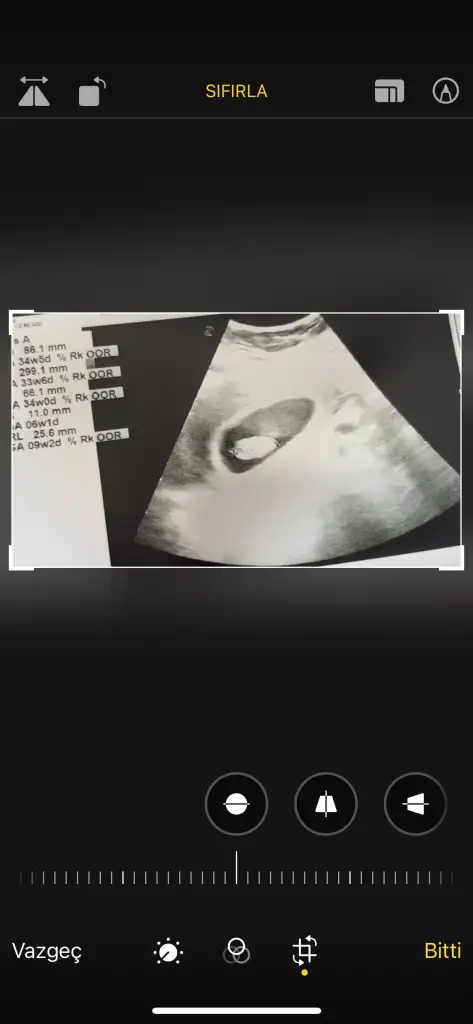

Çok sevindim hayırlı olsunBu yeni görüntümüz kızlarAllah’a şükür kalp atışını duyduk. Büyümüş dedi doktor 2 cm civarıymış. Miyomum da 7 cm olmuş düşük tehlikesi şu an için yok dedi miyomlar öyle birşey yapabiliyor çünkü Allah korusun cinsiyet tahmini yapar mısınız?